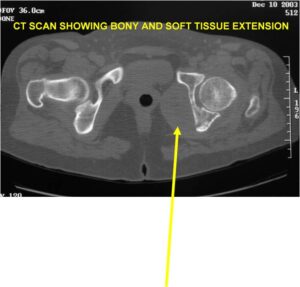

Radiology emulates pathology: Biphasic Tumor

- Second more aggressive area with bone destruction, lysis of calcification, soft tissue mass

- Cortical permeation and a soft tissue mass in 70% of cases

Ill-defined, lytic intraosseous lesion

- Or extraosseous soft tissue mass

Biological Behavior

- Very aggressive locally

- Frequently cortical perforation

- Mass is usually large if extraosseous extension occurs